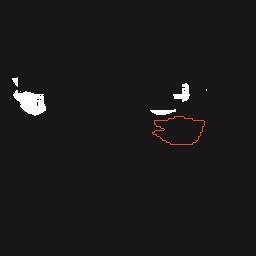

基于逐通道空间自适应选择核卷积与双向边界感知机制的乳腺超声图像病变分割网络

A Breast Ultrasound Images Lesion Segmentation Network Based on Channel-Wise Spatially Adaptive Selective Kernel Convolution and Bidirectional Boundary-Aware Mechanism

乳腺癌是全球女性最常见的恶性肿瘤之一,准确的病变分割对于乳腺癌的早期诊断与治疗具有重要意义。然而,由于病变形态的多样性以及超声成像机制的复杂性,现有基于深度学习的乳腺超声图像病变分割方法在分割准确性方面仍面临巨大挑战。为进一步提升乳腺超声图像中病变区域的分割精度,该文基于经典U-Net架构,提出了一种新型乳腺超声图像病变分割网络(CWSASKM-BBAM-Net)。首先,在网络中引入逐通道空间自适应选择核卷积模块(CWSASKM),根据不同通道的语义特征为每个空间位置自适应选择感受野大小,以增强多尺度信息的建模能力;然后,引入双向边界感知机制(BBAM),通过融合正向与反向注意力,对目标显著区域及其边界进行协同建模,同时逐步提升对非显著区域与病变区域的区分能力,以进一步强化边界信息的表达;最后,在3组公开乳腺超声图像数据集(BUSI、UDIAT和STU)上开展分割实验。结果表明:该方法在数据集BUSI上的杰卡德指数、精确率、召回率和Dice相似系数分别为71.97%、82.85%、81.40%和80.44%,较次优方法分别提升1.69、1.05、1.28和1.84个百分点;在数据集UDIAT上,这4项指标分别达到78.14%、88.31%、86.73%和86.10%,较次优方法分别提升了2.75、2.04、0.56和2.01个百分点;在外部数据集STU上,该方法也取得了优于其他方法的整体表现。实验结果表明,CWSASKM-BBAM-Net在乳腺超声图像分割任务中展现出更优的整体性能。